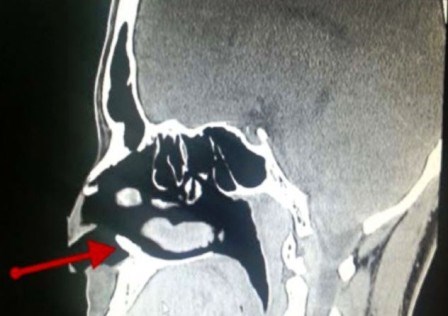

Báo cáo nghiên cứu do Tạp chí “Case Reports” được xuất bản ở Mỹ cho biết, đây là một chiếc răng khôn, thay vì mọc trong miệng thì nó lại nổi lên ở lỗ mũi gây nên hiện tượng chảy máu mũi.

Theo tờ Live Science, các bác sĩ ở bệnh viện quân y King Fahd tại Dhahran, Ả-rập Xê-út đã rất ngạc nhiên khi phát hiện thấy chiếc răng lại mọc trong lỗ mũi. Sau khi gây mê và tiến hành ca tiểu phẩu, chiếc răng trong lỗ mũi đã được loại bỏ thành công.

Bác sĩ John Hellstein, một trong những tác giả của bài nghiên cứu, giải thích rằng mặc dù hiếm gặp nhưng những chiếc răng khôn có thể phát triển gần răng cửa và trong một số trường hợp những chiếc răng khôn này có thể phát triển thẳng đứng lên phía mũi.